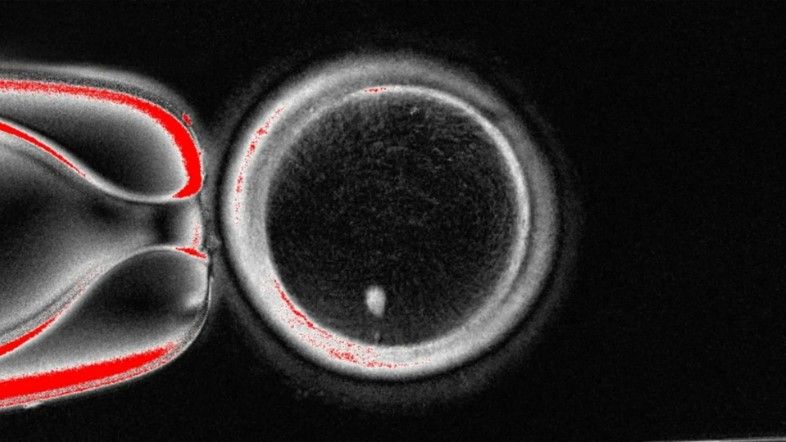

Emberi bőrsejtből vettek ki sejtmagot – a sejt azon részét, ami a genetikai információ nagy részét tartalmazza –, és donor petesejtbe ültették át, melyből eltávolították a saját sejtmagját. Így 82 működőképes emberi oocitát, azaz éretlen petesejtet állítottak elő, melyeket laboratóriumban megtermékenyítettek. Képünkön egy petesejt és egy bőrsejtmag látható megtermékenyítés előtt.